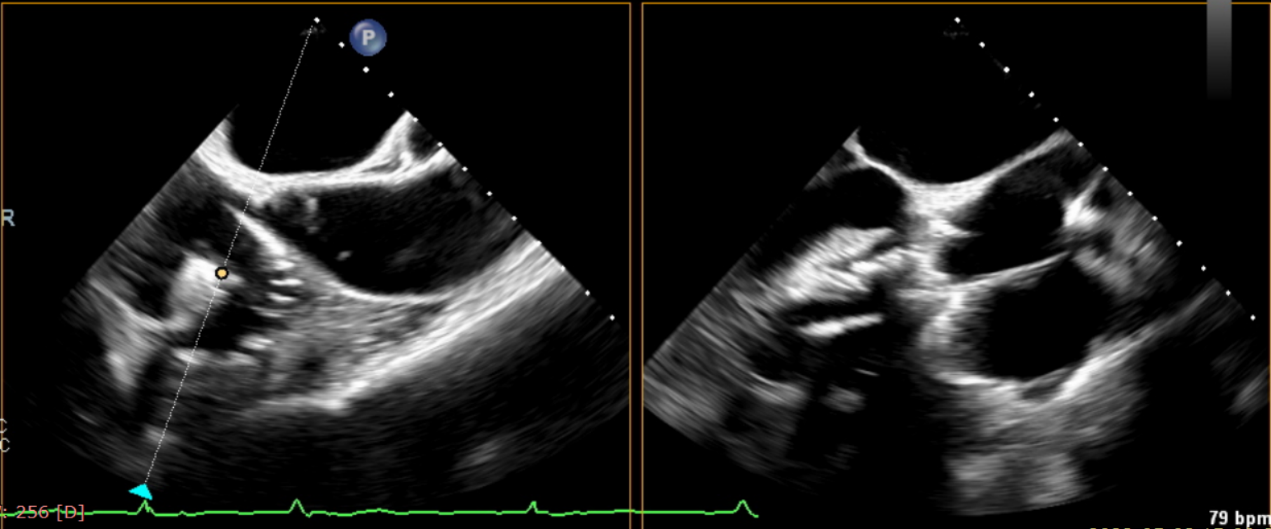

術(shù)前超聲提示大量三尖瓣反流

術(shù)中輸送器在超聲引導(dǎo)下調(diào)整位置

術(shù)后超聲提示無瓣周漏